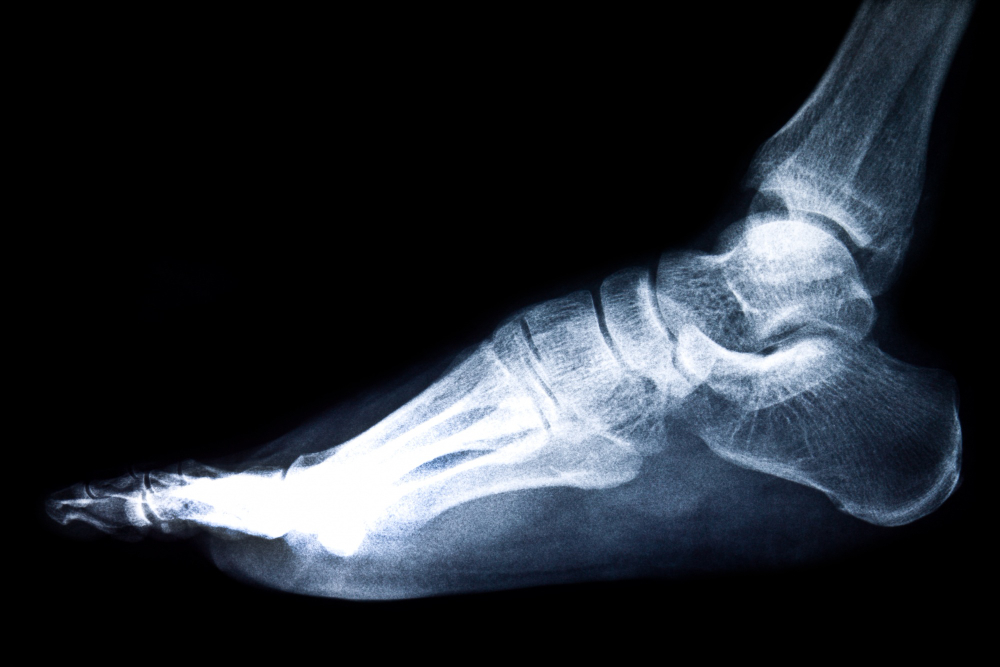

A CT scan of the left foot is a specialized imaging test that uses advanced X-ray technology to create detailed cross-sectional and 3D images of the bones and soft tissues within the foot. This scan is highly valuable for diagnosing various foot problems such as fractures, deformities, tumors, infections, and arthritis, especially when conventional X-rays do not provide sufficient detail. The CT scan can visualize complex bone structures like the tarsal bones, metatarsals, and phalanges, aiding in detecting bone alignment issues and subtle injuries. It is also essential for pre-surgical planning and postoperative assessment.